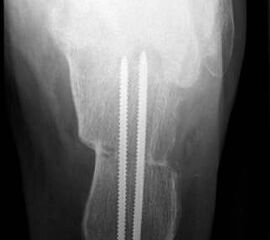

• Definitive Fixation über die dorsoplantare Querinzision mittels Schrauben (normale 3.5 mm Kortikalsischrauben sind hier völlig ausreichend).

• Kontrolle der korrekten Schraubenlage im BV (Abb. 3).

• Plantigrade Gipsruhigstellung für 6 bis 8 Wochen, 4 Wochen 0 kg und 4 Wochen 10 kg Teilbelastung führt zu einer sicheren Konsolidation des Knochens.